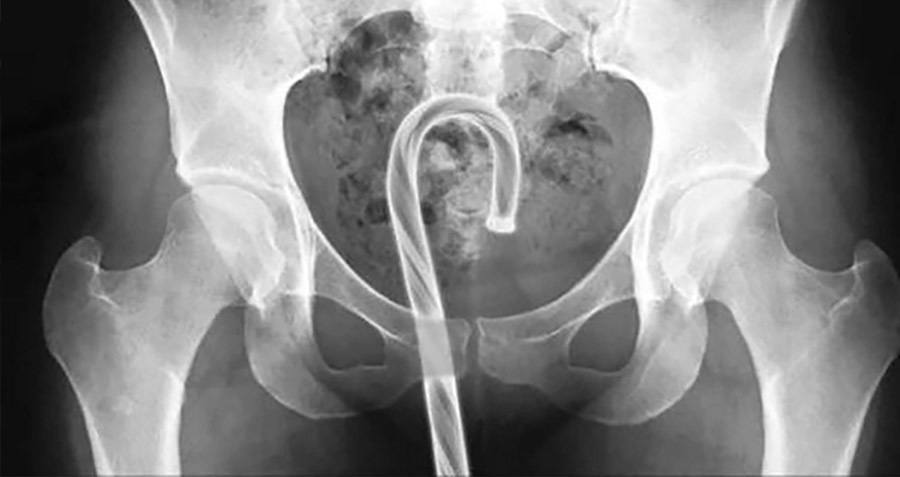

- Slow-Roll the national health care plan. Phase it in a few areas at a time. Nothing jarringly huge. Take one service and subsidize it. Radiology. Every x-ray, CT Scan, MRI is paid for by the American Government. Soon you’ll see what works and what doesn’t, the potential areas of corruption, and who stuck what in their where-now?